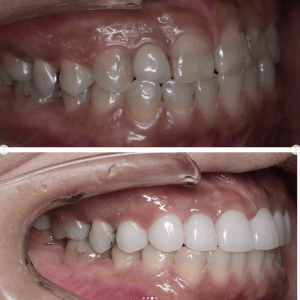

Case005 – ワイヤー矯正

片顎抜歯を行い、主に上の前歯の歯並びを矯正した症例です。